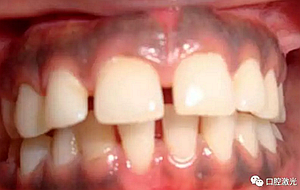

患者22歲,女性,主訴牙齦發(fā)黑??谇粰z查顯示牙齦部位呈黑色,但軟組織健康,沒有表皮粗糙或水腫現(xiàn)象。計(jì)劃使用半導(dǎo)體激光進(jìn)行治療。手術(shù)前患者無需表麻或局麻。采用光纖接觸方式,激光功率設(shè)定為1.5W至2W,連續(xù)模式。氣化黑色牙齦區(qū)域上皮組織。不斷重復(fù)該過程,直至足夠深度的牙齦軟組織表皮被去除干凈?;颊咝g(shù)后需采用漱口水進(jìn)行口腔護(hù)理。

術(shù)前